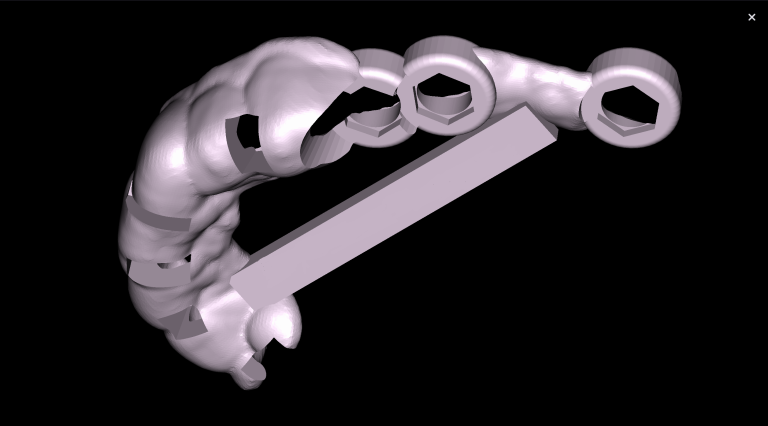

Task: Plan the implant treatment for the replacement of teeth 16 (Universal 3) and 17 (Universal 2), reduce the time required for surgical template fabrication, and improve the accuracy of its fit. Using the “STL” module of Diagnocat, it is possible to create a 3D reconstruction of cone-beam computed tomography (CBCT) and virtual models of templates. To achieve this, intraoral scan data is uploaded into the module, and a suitable CBCT is selected for merging.

Solution: Diagnocat AI provides an advanced solution for identifying CBCT structures using machine learning and artificial intelligence technologies. By combining STL and DICOM data in a unified coordinate system, Diagnocat minimizes errors when creating template models.